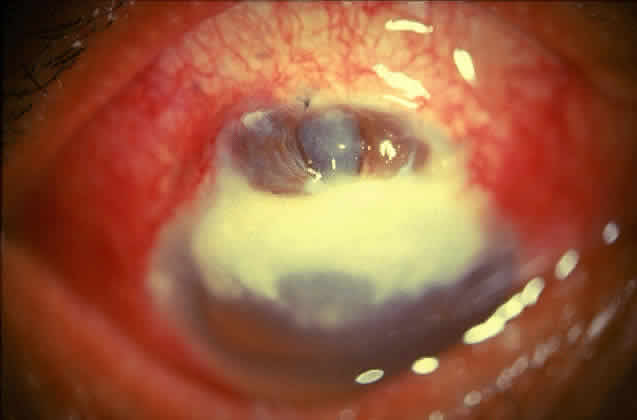

Active corneal infections in advanced stages are encountered more often by corneal surgeons in developing countries compared with their counterparts in developed countries (Fig. 8). The extent of corneal involvement associated with other intraocular damage often compromises the success of corneal transplantation. In a series from our institution, the success rate for graft clarity was poorer24 compared with other series.25 Ophthalmologists involved in corneal surgery should be familiar with this information and be prepared for the necessary intraoperative manipulations (Fig. 9).

Fig. 8. Corneal ulcer with extensive necrosis and perforation in the superior part.